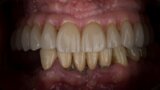

MAGICAL All on FOUR